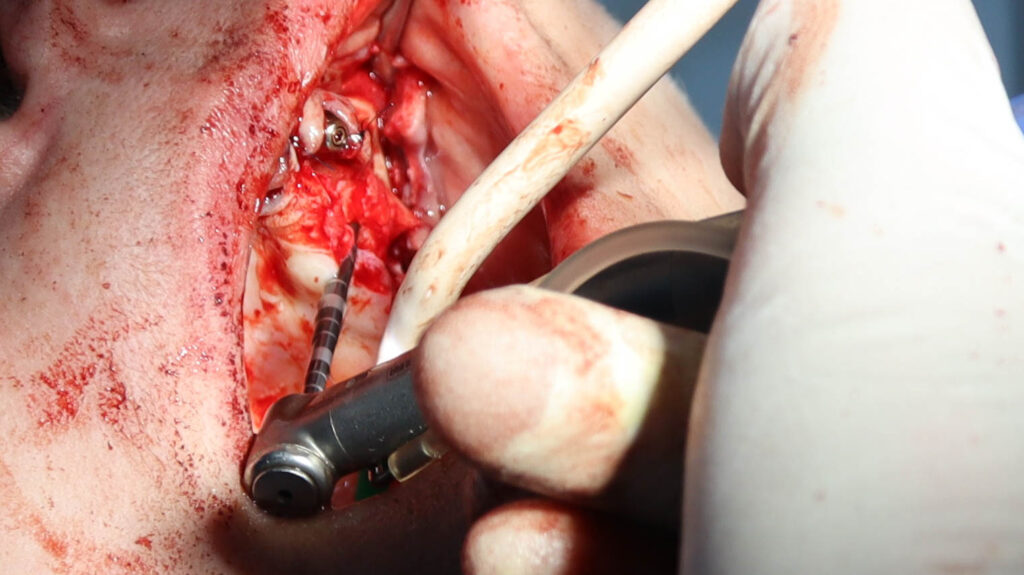

Фиксации имплантата внутри костной ткани (торк).

Это фото может содержать тяжелый для восприятия контент

процесс имплантации